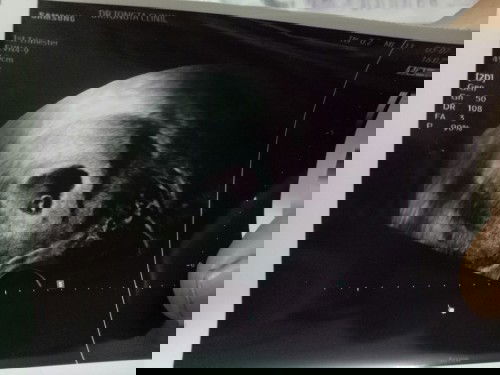

6สัปดาห์ หัวใจของหนูกระพริบแล้วนะคะ 😊😊😊